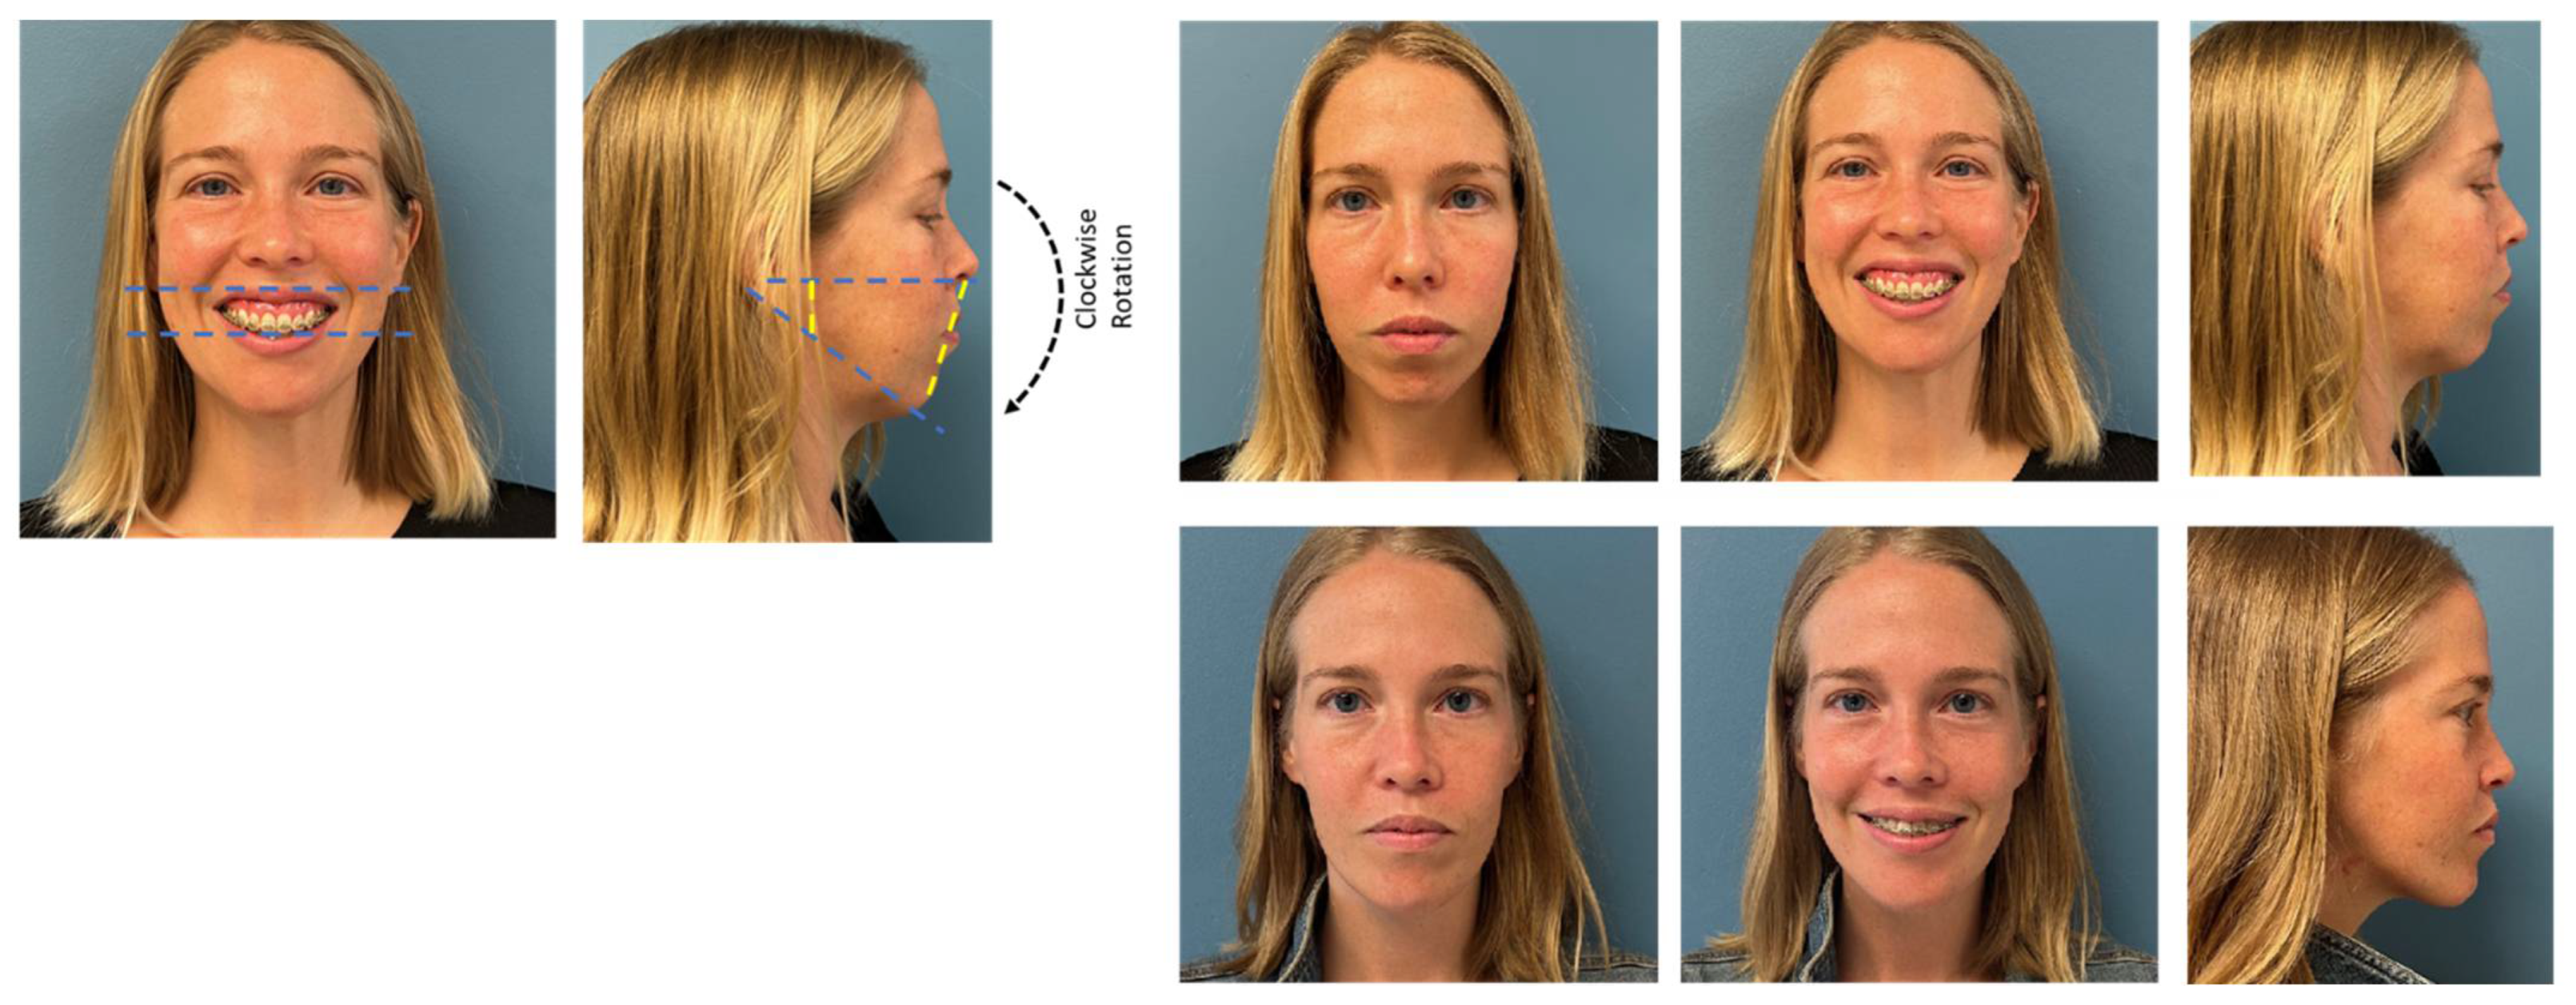

3.2. Surgery First Protocol (Figure 5)

- Wannalerkngam, C.; Sinha, S.P.; Tran-Duy, T.D.; Wen-Ching Ko, E.; Chen, Y.R.; Huang, C.S. Does Clockwise Rotation of Maxillomandibular Complex Using Surgery-First Approach to Correct Mandibular Prognathism Improve Facial Appearance? J. Oral Maxillofac. Surg. 2023, 81, 32–41. [Google Scholar] [CrossRef] [PubMed]